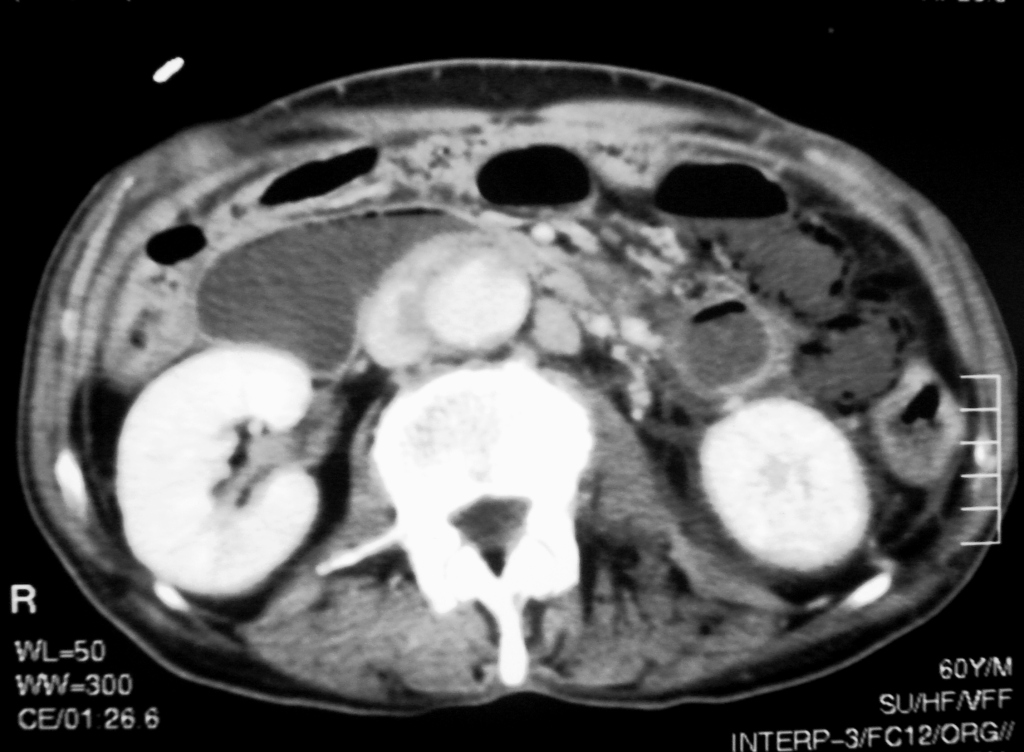

We describe the case of a 60-year-old diabetic man who was admitted to our hospital with keto-acidosis and rapidly developed sepsis and a mycotic abdominal aortic aneurysm (AAA) with branch involvement. Early and late findings on serial computed tomography (CT) examinations are presented. Awareness and recognition of early imaging findings associated with infectious aortitis and serial CT examination in cases of patients with sepsis and predisposing factors are essential for prompt diagnosis and treatment.